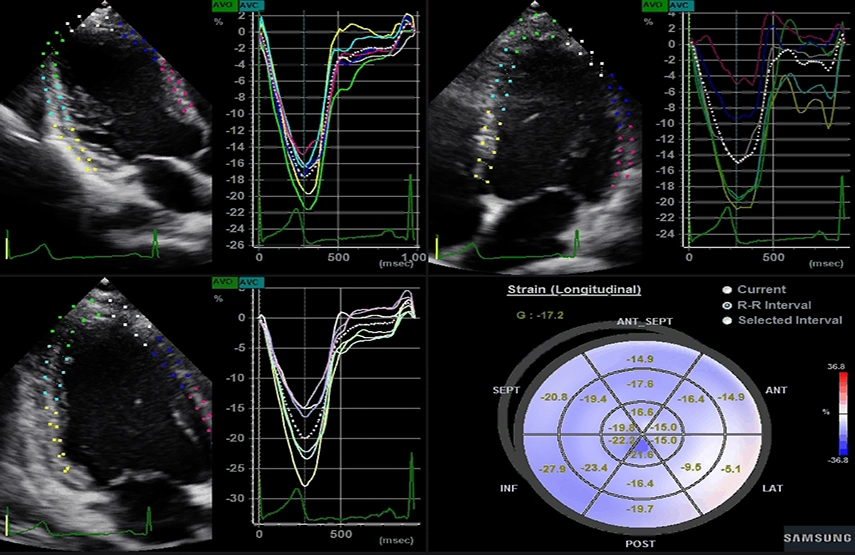

- Strain+ – недоплеровская методика количественной оценки глобальной и локальной сократимости левого желудочка сердца;

- Strain+ - это количественный метод оценки глобальной и локальной сократимости стенок левого желудочка (ЛЖ). Достаточно указать три точки, и Strain+ автоматически создаст контур стенок желудочка с расчетом данных деформации. В режиме Strain+ на экран выводятся четыре изображения для быстрой и точной оценки функции ЛЖ: три стандартных проекции ЛЖ и диаграмма «Бычий глаз». Функция Strain+ от Samsung улучшает эффективность диагностики благодаря простому интерфейсу, наглядной визуализации и вспомогательным указателям.

Strain+